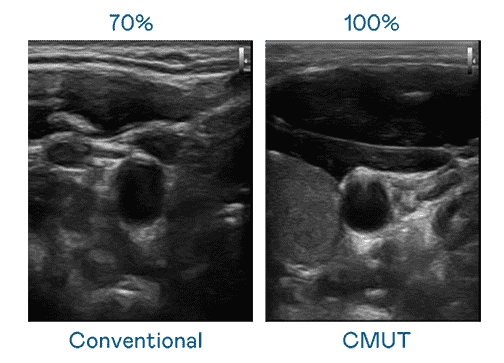

CMUT 技术是一种用电容式微机电元件来产生超音波讯号的技术。。与传统 PZT 压电式技术相比,,,,CMUT 频宽增加 30%,,,更宽频的超音波讯号让影像解析度大幅提升,,是实现高影像品质医疗超音波扫描、、、促进精准医疗发展的关键技术。。。

超音波影像的解析度高低,,,首先取决于探头能发出的讯号频宽。。Wepay CMUT 可提供高清晰的超音波讯号,,,提供高频宽、、高灵敏度、、、、影像纹理细节更高的超音波影像,,,协助医护人员缩短影像判读时间及利用精准的医疗影像进行诊断。。。